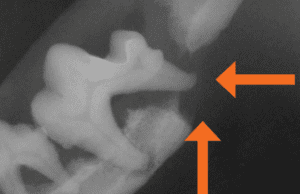

After years of anesthesia-free dentistry, the dog in this image lost so much bone structure due to undetected periodontal disease that it resulted in a grade 3 furcation exposure (the probe goes through the furcation area from one side of the jaw to the other).

Figure 2 Consequences of NAD